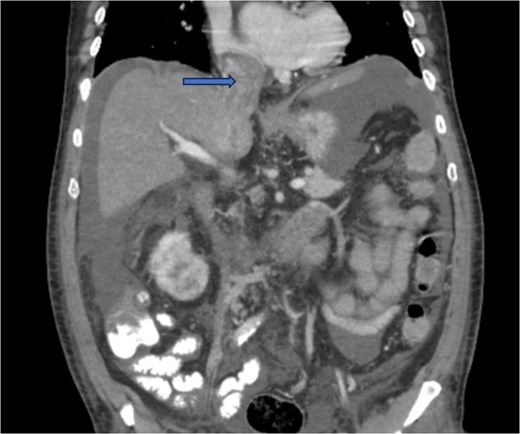

Diagnostic imaging began with a chest X-ray that indicated bilateral pleural effusions. An abdominal ultrasound detected a 4.6 × 4.2 × 4.3 cm echogenic lesion in the right hepatic lobe. Further imaging with a computed tomography (CT) scan of the chest, abdomen, and pelvis revealed a large mass originating from the posterior aspect of the right mid-kidney consistent with RCC (Fig. 1). The mass associated with thrombus extended into the renal sinus and collecting system, traveled along the right renal vein to the inferior vena cava (IVC), and projected into the right atrium (Figs 2 and 3). During hospitalization, bilateral lower extremity pain led to the diagnosis of bilateral deep vein thromboses via duplex venous ultrasound. Echocardiography showed normal left ventricular ejection fraction, impaired diastolic filling, mildly increased ventricular wall thickness, and an echogenic mass extending from the right atrium into the IVC consistent with the tumor thrombus.

CT chest abdomen and pelvis with contrast showing middle portion of right with tumor during venous phase venous phase.